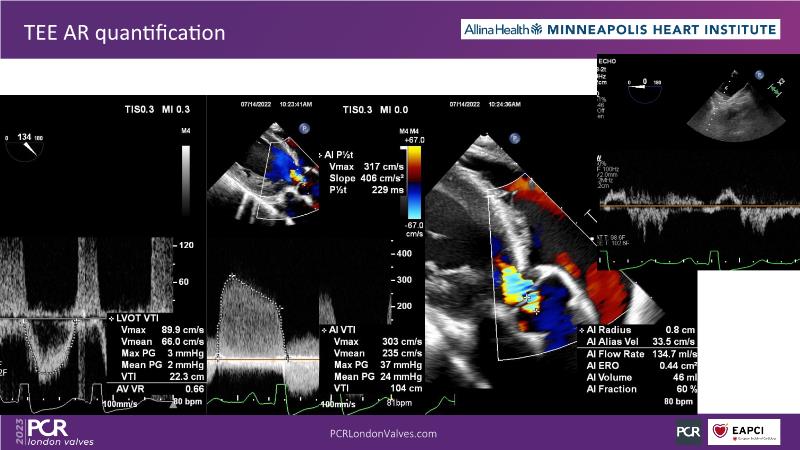

- To understand the challenges of imaging for aortic regurgitation and how it can lead to underdiagnosis